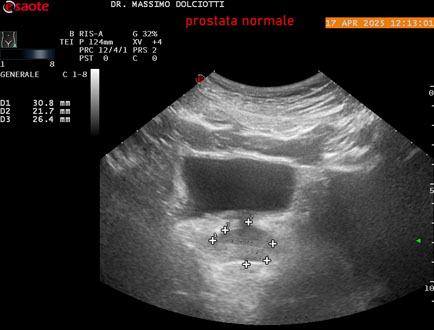

Data inserimento: 01/10/2025

Ecografia del: 17/04/2025

Strumento: Esaote MyLab Eight

Sonda: Convex Multifrequenza 1-8 MHz, Endocavitaria Multifrequenza 3-9 MHz e 3-13 MHz

Età Paziente: M 35 anni

Motivazione dell'esame: disuria.

Commento all'esame: le immagini ed il video documentano la prostata di ecostruttura regolare e morfovolumetria normale con diametro trasversale di 40 mm, diametro anteroposteriore di 21 mm e diametro longitudinale di 43 mm, con volume prostatico calcolato di 18 cc (v.n. < 20 cc), il profilo prostatico è regolare e netto, non si documentano calcificazioni intraghiandolari, la vascolarizzazione della ghiandola è normale. La vescicola seminale destra presenta diametro longitudinale di 44,4 x 7,8 mm, la vescicale seminale sinistra ha diametro longitudinale di 45,3 mm x 7,2 mm.

Conclusioni: prostata normale (normal prostate).